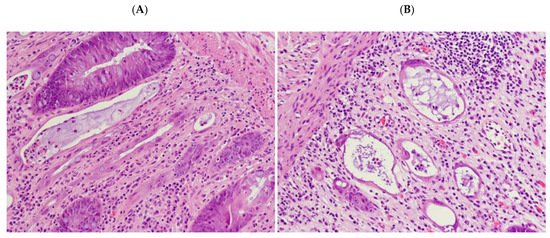

2.2. Radiation-Induced Morphological Features

2.4. “Dysplastic-Like” Features